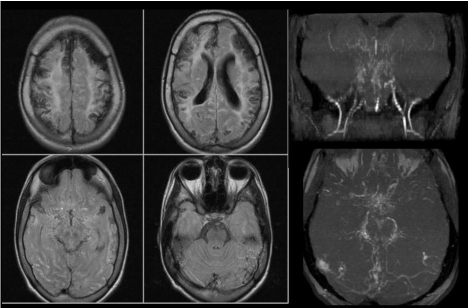

A 23-year-old Caucasian woman had presented to SARAH Hospital at age 3 with history of 3 ischemic strokes at 10, 12 and 16 months of age, all in the carotid artery topography. Intracranial magnetic resonance angiography revealed bilateral carotid artery occlusion and the presence of increased leptomeningeal collaterals (Figure 1), leading to a diagnosis of Moyamoya syndrome. Infectious and thrombophilic conditions were ruled out. We also ruled out the presence of the human immunodeficiency virus, syphilis, Chagas disease, lupus, antiphospholipid syndrome, protein C and S deficiency, prothrombin mutation, antithrombin III deficiency and Factor V Leiden mutation. No cardiac and/or sickle cell disease was detected. She showed a mild elevation of her serum homocysteine levels (19.4 µmol/L), reference range indicating values within 15 µmol/L) and a homozygous MTHFR gene mutation (677TT polymorphism). The Ethics Committee of SARAH Hospital approved this case report based on Brazilian regulations.

Figure 1. Fluid-attenuated inversion recovery (FLAIR) axial images showing gliosis and cortical necrosis involving the frontal and parietal lobes.

There is subarachnoid hyperintensity observed possibly related to the presence of leptomeningeal collateral vessels.

Time-of-flight-magnetic resonance angiography (TOF-MRA) images: Coronal view: the middle meningeal arteries are observed to be prominent. Internal carotid arteries showing flow interruption in the petrous portion. There is occlusion of the middle cerebral arteries. Hyperintensities corresponding to moyamoya vessels are observed.

Axial view: Moyamoya vessels are identified along the interpeduncular and perimesencephalic cisterns and also along the Sylvian fissure.